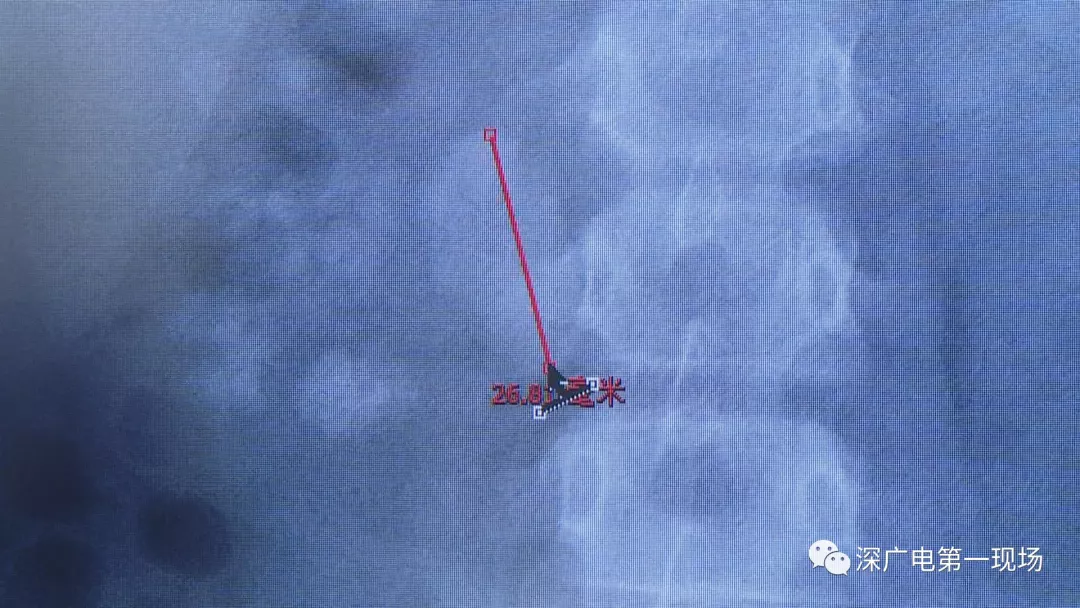

在X光圖像下,醫(yī)生發(fā)現(xiàn)小軒的雙側(cè)腎臟都內(nèi)藏乾坤,密密麻麻的分布著大小不等的結(jié)石。

像這種情況

連見(jiàn)多識(shí)廣的醫(yī)生也直呼不可思議

醫(yī)生這么解釋?zhuān)和ǔG闆r下,成人只要有0.5厘米大小的結(jié)石造成尿路梗阻,就需要及時(shí)治療。

小軒這種情況,其中,最大的結(jié)石長(zhǎng)約2.7厘米,寬約1.7厘米,體積堪比鵪鶉蛋,不但造成了尿路堵塞,還導(dǎo)致了右腎中度積水。